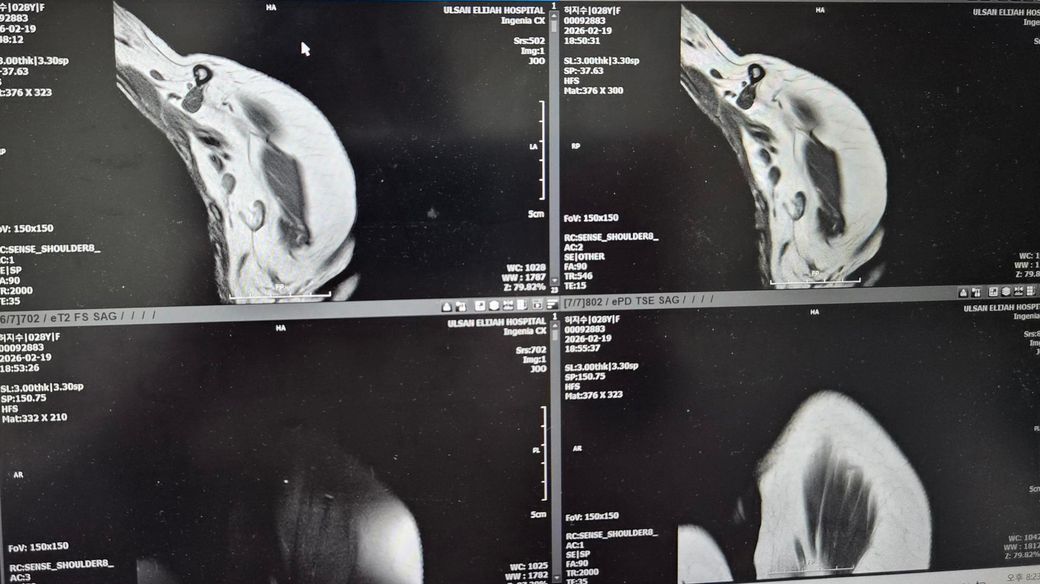

어께MRI판독좀 해주세요!어떤가요?

제가 2024년도 어께로 넘어진 이유로 1년10개월동안 아파서 MRI찍고 무섭다고해서

뺄수밖에 없었어요.누워서 안정취하다가 수납하고갔어요.그다음날 종합병원정형외과가서 접수하고 기다렸어요. 들어갔더니 의사가 힘줄에는 다 이상이 없데요.뼈가 (견봉쪽?)골절되면서 붙으면서 뼈가 위로조금 오른쪽이랑 다르게 올라갔데요 그래서 아프면 주사맞자고해서 주사대기중이였어요.옷갈아입고 기다렸어요.

올려주신 MRI사진은 화면 촬영본이라 정확한 판돈까지는 어렵지만, 담당 의사가 말씀하신 것처럼 회전근개 힘줄 자체의 명확한 완전파열 소견은 없어 보이는 경우로 이해됩니다. 설명해주신 내용상 어깨 위쪽 뼈 쪽 골절이 치유되는 과정에서 약간 위로 붙어 형태가 변형되었고, 그로인해 어깨를 들때 힘줄과 뼈 사이 공간이 좁아져 마찰이 생기는 충돌 증후군 형태일 가능성이 높아 보입니다. 주사 치료는 보통 염증을 줄이기 위한 스테로이드+국소 마취제 주사이며, 약물이 하얗고 양이 많으며 들어갈때 아픈것은 비교적 흔합니다. 주사 맞은 당일저녁에 헬스장에서 찌릿한 통증이 생긴것은 힘줄이 새로 찢어졌다기보다는 주사 후 자극+기존 충돌부위 자극 때문일 가능성이 훨씬 큽니다. 현재로서는 최소 1주일 정도는 상체웨이트 운동을 쉬고, 얼음찜질과 가벼운 가동범위 운동만 하는것이 좋습니다. 이후 통증이 줄어들면 가벼운 밴드 운동부터 재개하는 것이 안전합니다. 빠른쾌유를 빕니다!

올려주신 사진은 정확한 컷이 아니라 판독이 어렵습니다

올려주신 내용 따르면 견쇄부위 언급이 있습니다

쇄골을따라가면서.견쇄관절 볼록 나온 부분에 압통이 있으신 지 확인해보시면 좋을 것 같아요